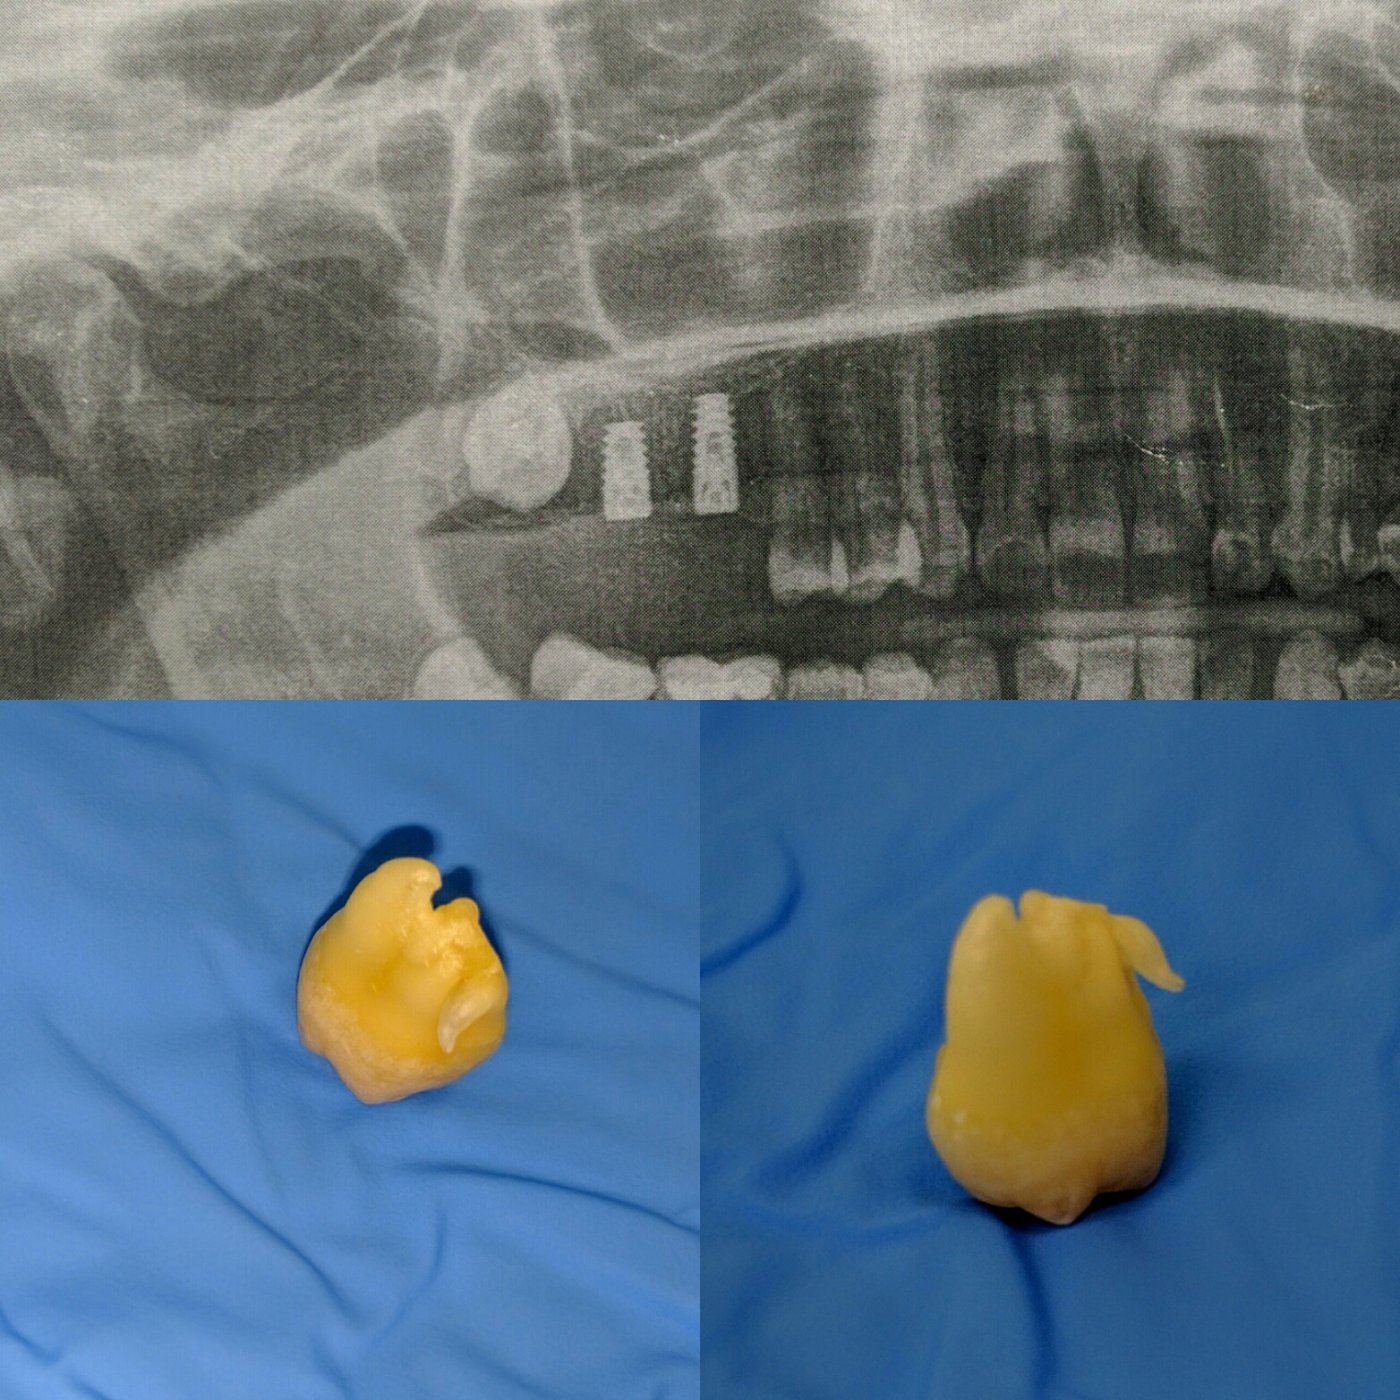

Имплантацией занимаюсь с 2013 года, преимущественно с корейскими системами имплантатов Dentium, Osstem.

Так же есть опыт в установке израйльских имплантатов Noris, Mis, Alpha Bio, и швейцарских имплантатов SIC.

Из навыков: открытый и закрытый синус лифтинг, одномоментная имплантация , расщепление альвеолярного гребня, sausage technique и другая направленная костная регенирация, опыт в работе с титановыми сетками на имплантатах Osstem система Smart Builder, мягкотканная пластика десны, пародонтологические операции. Удаление зубов любой сложности, чтение клкт (3D) и составления рационального плана лечения, стремление расти и развиваться профессионально!